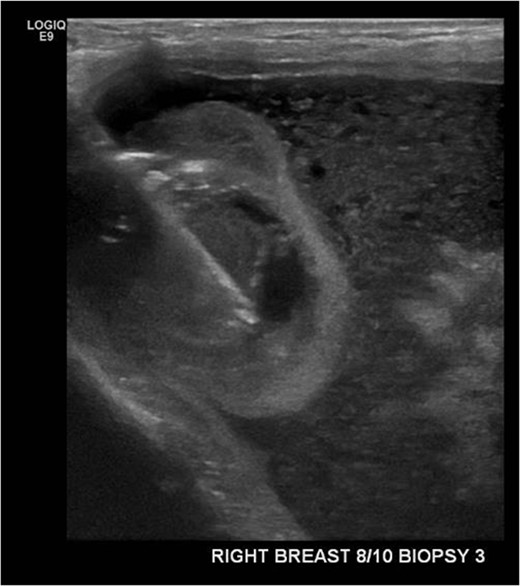

An ultrasound-guided core biopsy of the right breast intracapscular lesion was performed (Fig. 2). The histology showed mostly fibrinous material with a small amount of exogenous foreign material, with no evidence of granulomatous inflammation or malignancy.

Ultrasound-guided core biopsy of the right intracapsular breast lesion.